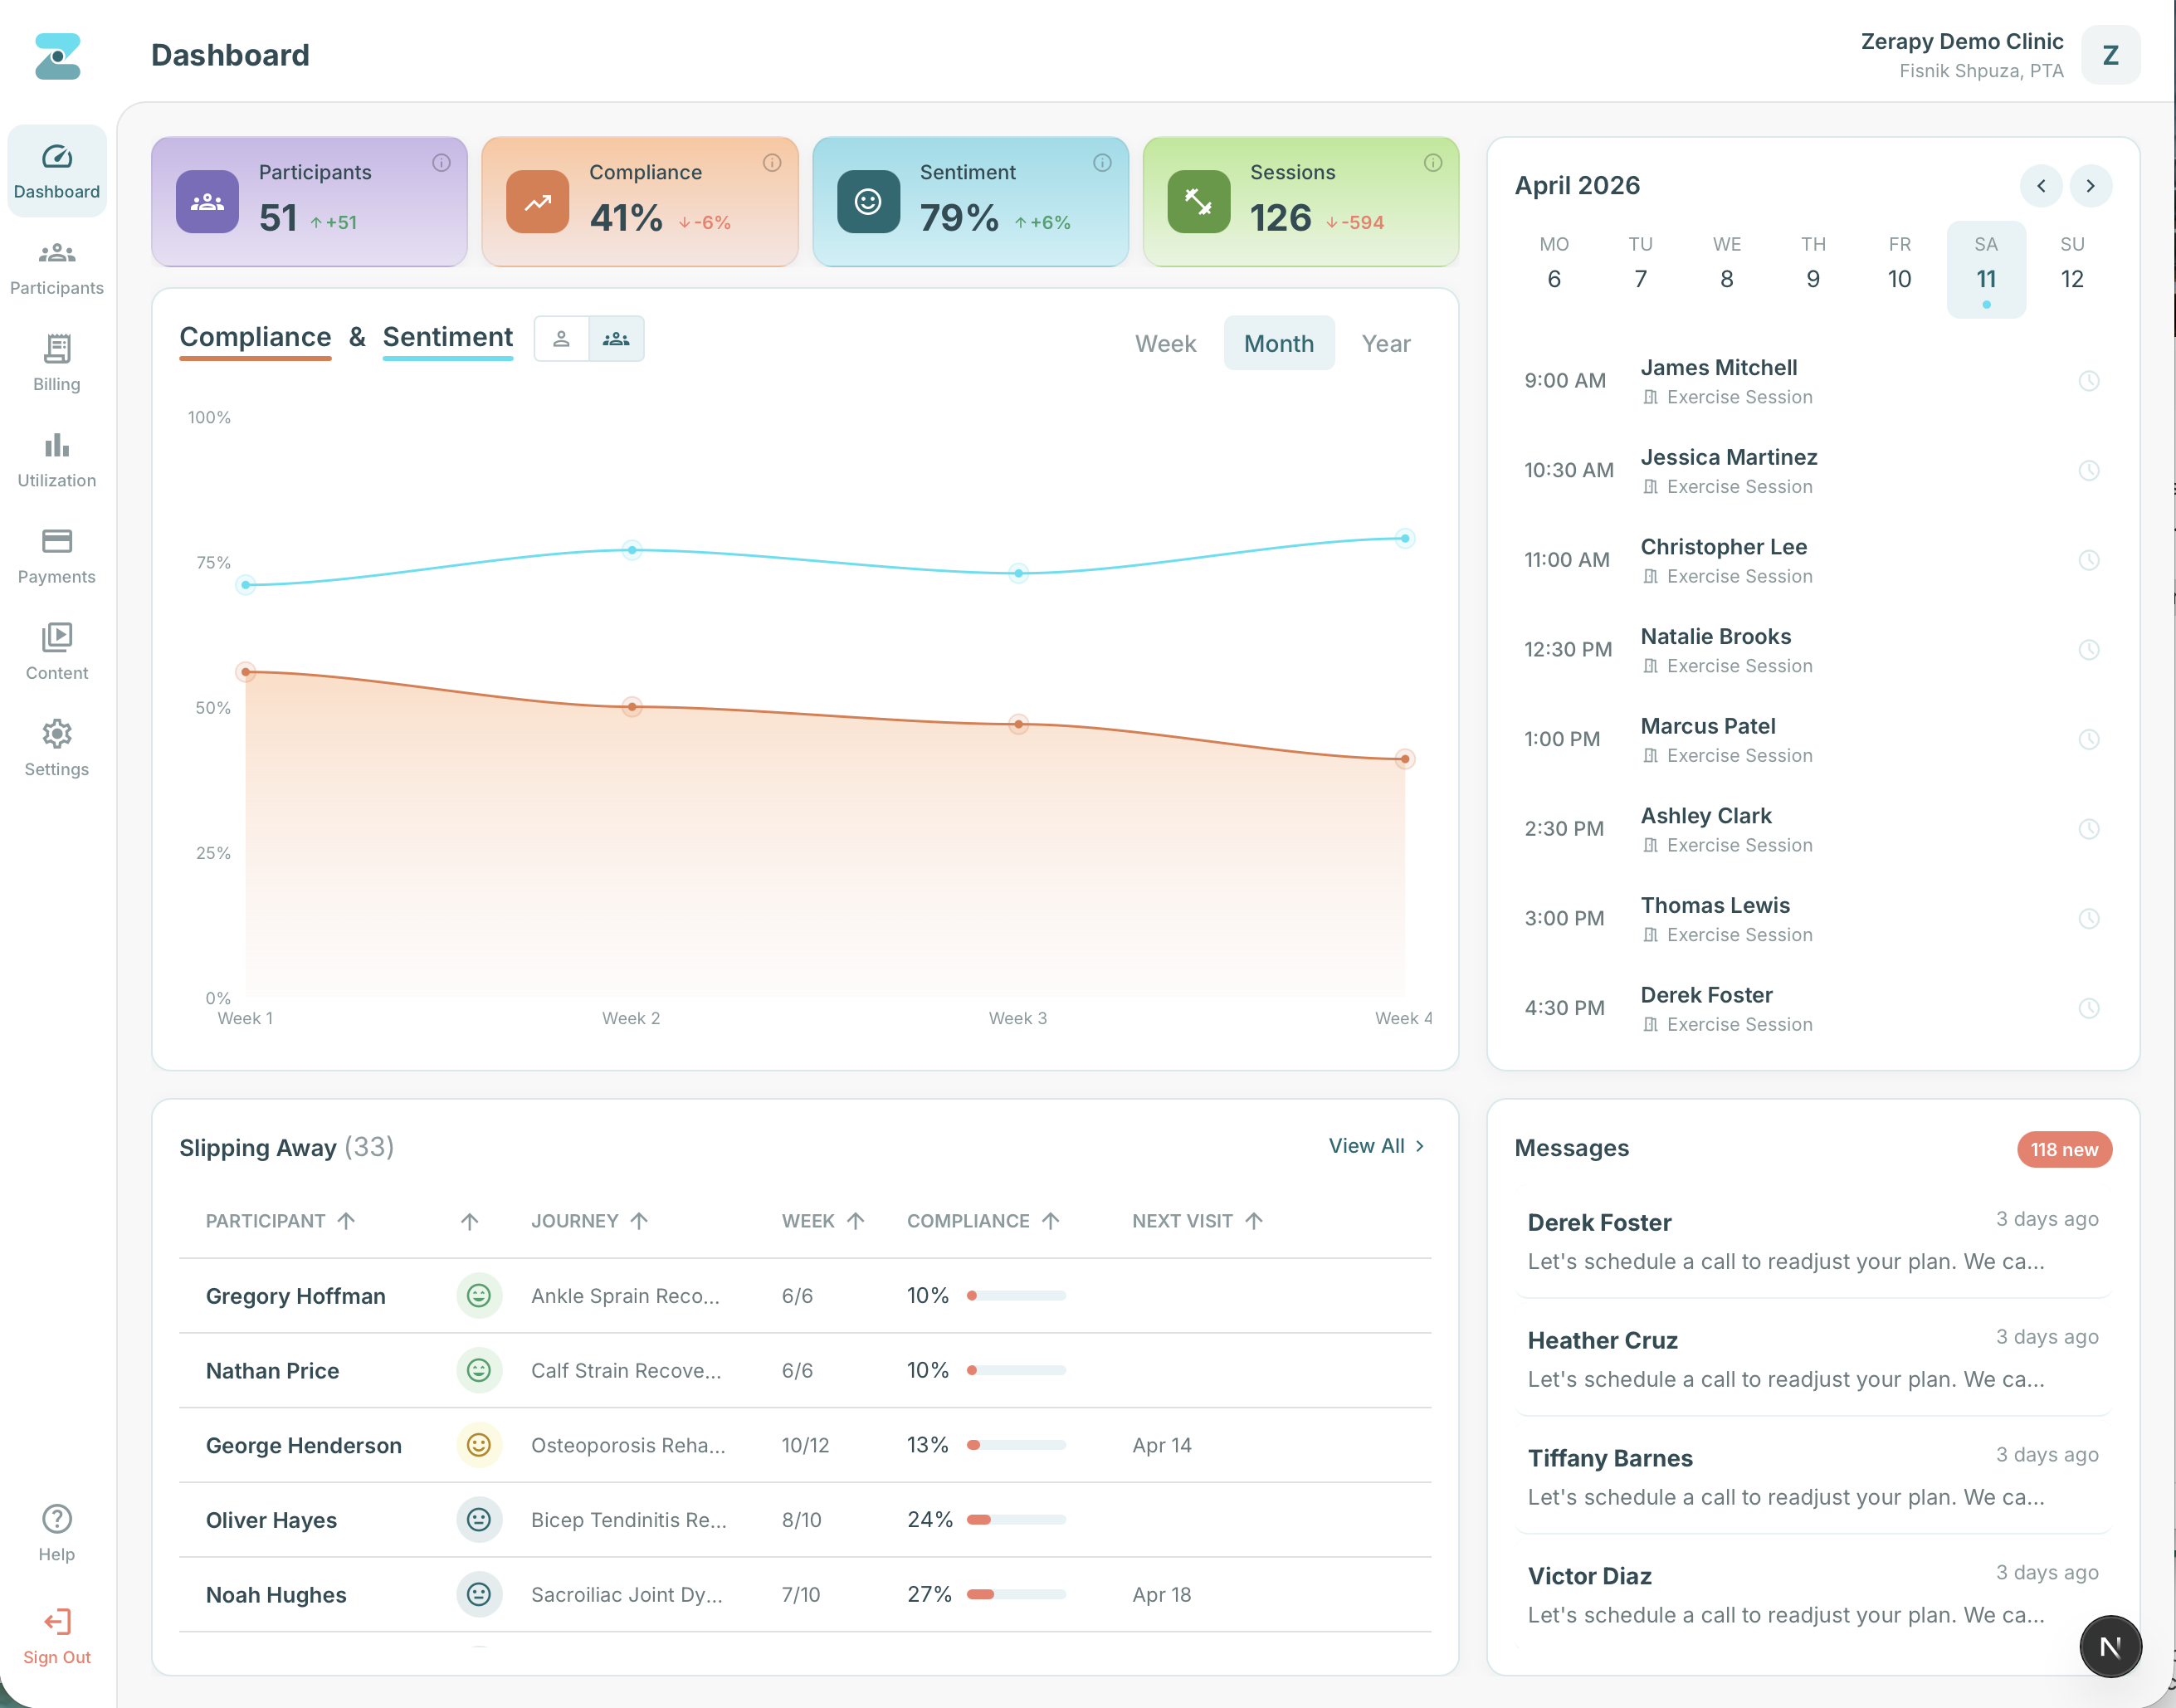

One AI that writes your SOAP notes, automates RTM documentation, and turns patient engagement into revenue. Built for physical therapy from day one.

Zera learns as your practice grows. One system for documentation, exercise programs, remote monitoring, and compliance.

RTM documentation created automatically when patients engage. Compliance tracking and automated billing.